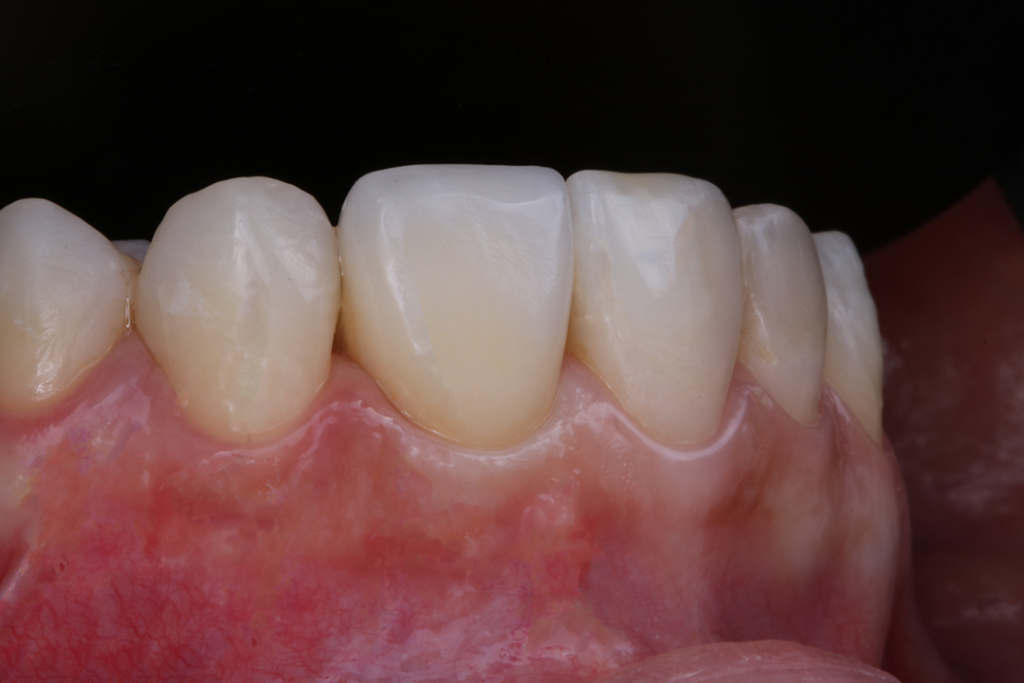

Contudo, após finalizado a coroa e baseado nas evidências clínicas e científicas, concluo que devemos obedecer a sequência correta do tratamento proposto, saber identificar a qualidade do tecido mole, indicar pilares que favoreçam a migração e acomodação do tecido e respeitar os limites de cada caso. Fig.10A/B/C